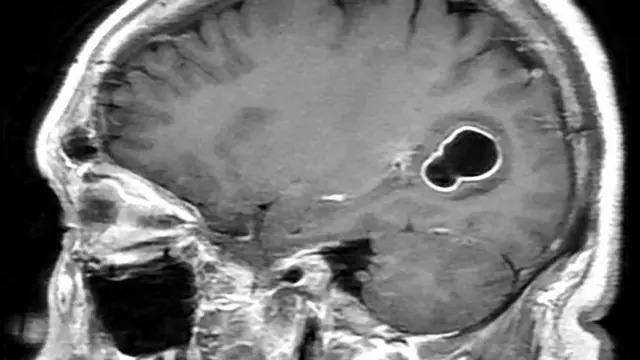

मायग्रेनवर उपचारांसाठी गेल्यावर धक्कादायक निदान, मेंदूत आढळले जंत

फोटो स्रोत, American Journal of Case Reports

अमेरिकेत काही दिवसांपूर्वी एक व्यक्ती डॉक्टरांकडे आली होती. मला सतत मायग्रेनचा त्रास होतोय, असं त्यांनी सांगितलं. स्कॅन केल्यानंतर डॉक्टरांना त्यांच्या मेंदूत चक्क जंत आढळले.

लांबलचक जंत एका रिबिनसारखे गुंडाळलेल्या अवस्थतेत होते.

अमेरिकेतील 52 वर्षीय पीडितेला मायग्रेनचा त्रास असह्य झाला होता. औषधांनीही काम होत नसल्याने त्यांनी डॉक्टरांचा सल्ला घेतला. तेव्हा ही बाब समोर आली आहे.

त्यानंतर डॉक्टरांनी स्कॅन केले आणि त्याच्या मेंदूमध्ये जंत आढळल्याची धक्कादायक माहिती समोर आली.

या जंतांमुळे पीडितेला सिस्टोसेरकोसिस आजार झाला होता.